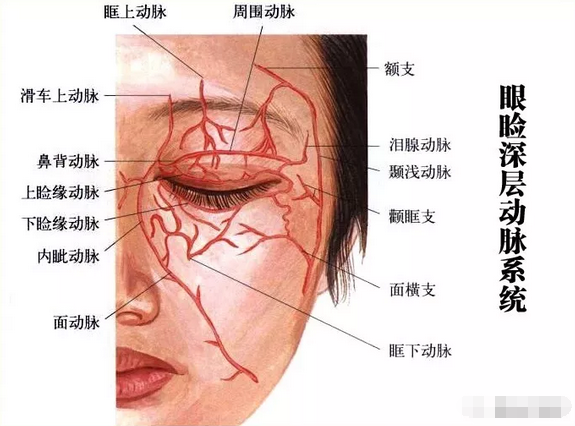

图l面部血管示意4.防治策略目前对于失明病例尚无成熟的治疗方法.

同时,鼻部的血液供应非常丰富,鼻子的血管贯穿面部构成了复杂而广泛的

【惟视诊室】面部注射玻尿酸,1小时后失明!